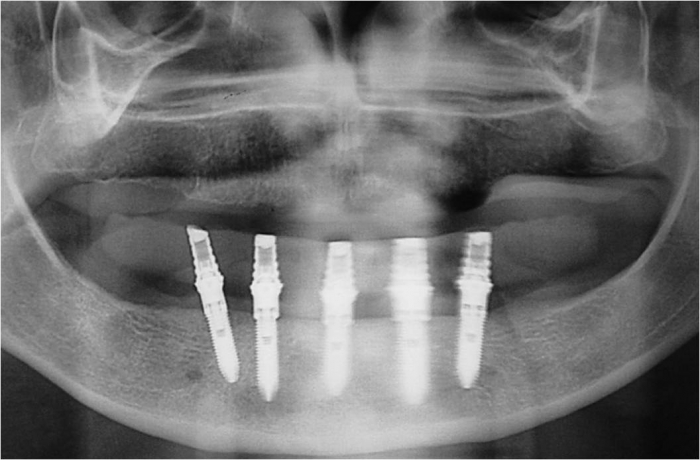

Raio X dos implantes inferiores - Clínica Cliniface

Raio X dos implantes inferiores